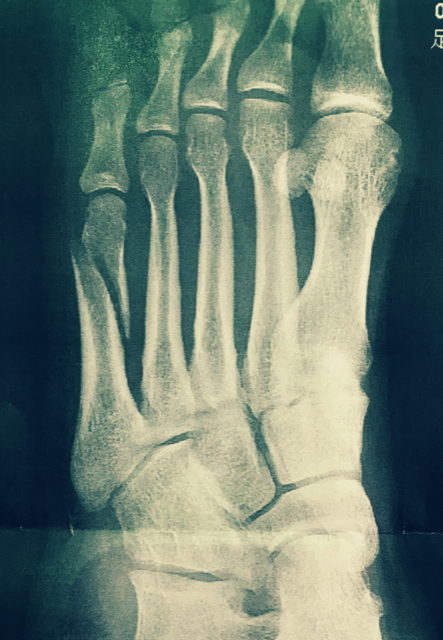

実はフジモト2月19日の夜に骨折しました。

左足の小指ちゃん側足の甲

(第5中足骨というらしい)をボッキリいきました。

なかなかの思い切りのいい折れ方

全治3ヶ月をいいわたされました。